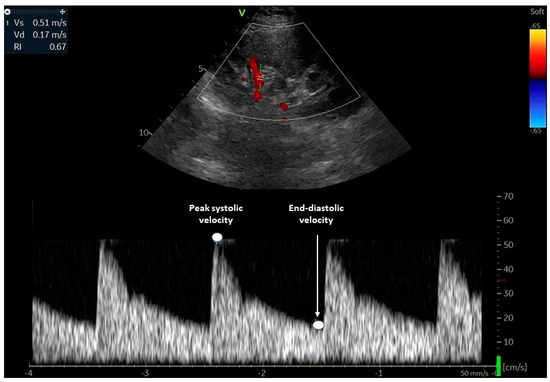

RRI = (Peak Systolic Velocity - Peak Diastolic Velocity) / Peak Systolic Velocity Calculator Diagram

Renal resistive index (RRI) is calculated using pulse wave doppler over the renal artery within the renal cortex.

Renal resistive index is an assessment of the peak systolic and end diastolic flow through the renal artery at the level of the renal cortex. In critically ill and trauma patients, it is a reliable predictor of acute kidney injury. In shock, the kidney is often the first organ that we see signs of malperfusion in, often manifesting as low urine output.

A normal value for renal resistive index is <0.7, with values >0.7 predictive of acute kidney injury.